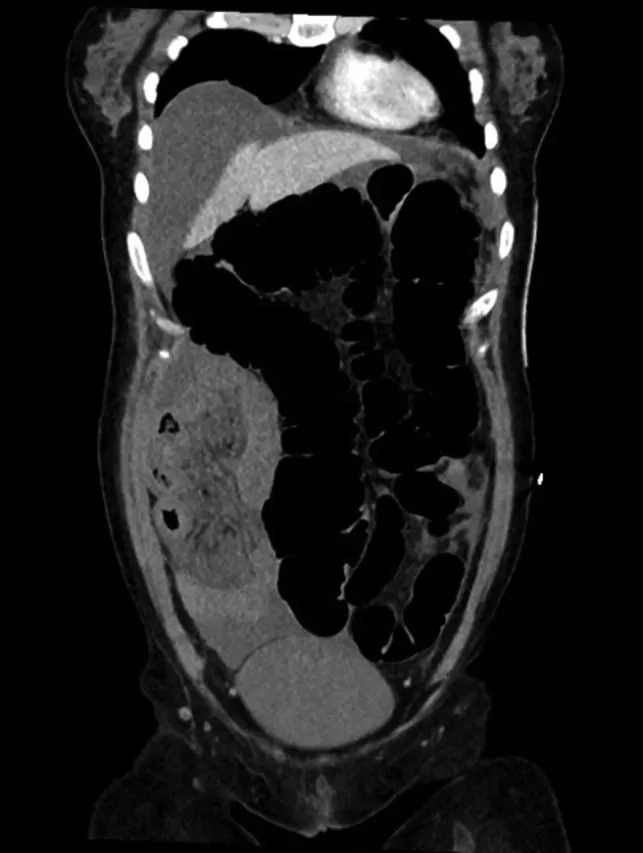

На следующее утро пациентка пожаловалась на боли в животе. Чтобы исключить перфорацию, была проведена рентгенография органов брюшной полости. Выявлен газ в петлях кишки без свободного газа в брюшной полости (рис. 1) Состояние пациентки в течение дня ухудшалось: возникла тахикардия до 134 ударов в минуту и упало давление до 67/47 мм рт. ст. При РКТ органов брюшной полости обнаружена перицекальная грыжа с петлями подвздошной кишки, расположенными по ходу правой половины ободочной кишки, с признаками ишемии (рис. 2), а также умеренное количество свободной жидкости без свободного газа (рис. 3).

Рисунок 3 [1].